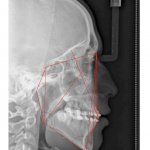

- Tweed